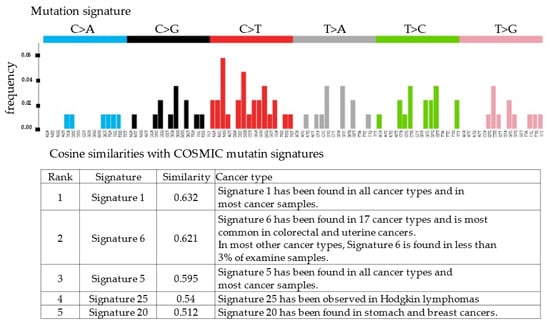

RecQ like heliccase4 (RECQL4), CNTNAP2, and PRDM2 variants, which are tumor suppressor genes, were detected by whole-exome sequencing. All three variants were germline variants and revealed a somatic uniparental disomy (somatic UPD). Variant positions and variant allele frequencies are shown in Table 1. However, no actionable variants and no copy number alterations were identified in the known oncogenes. The copy number plot was normal and therefore, the tumor was considered homologous recombination proficient (HRP) (Figure 4). Moreover, it was determined to be microsatellite-stable given that the microsatellite instability was 3.82%. The tumor mutation rate was 1.73 SNVs/Mbp, indicating no tumor mutation burden. We also examined the mutation signatures of the malignant struma ovarii. The most prevalent mutational signature was signature 1, which has been found in all cancer types and in most cancer samples (Figure 5).

Figure 5.

Cosine similarities with COSMIC mutation signatures. Signature 1 showed the highest similarities with the mutation profile of the patient.